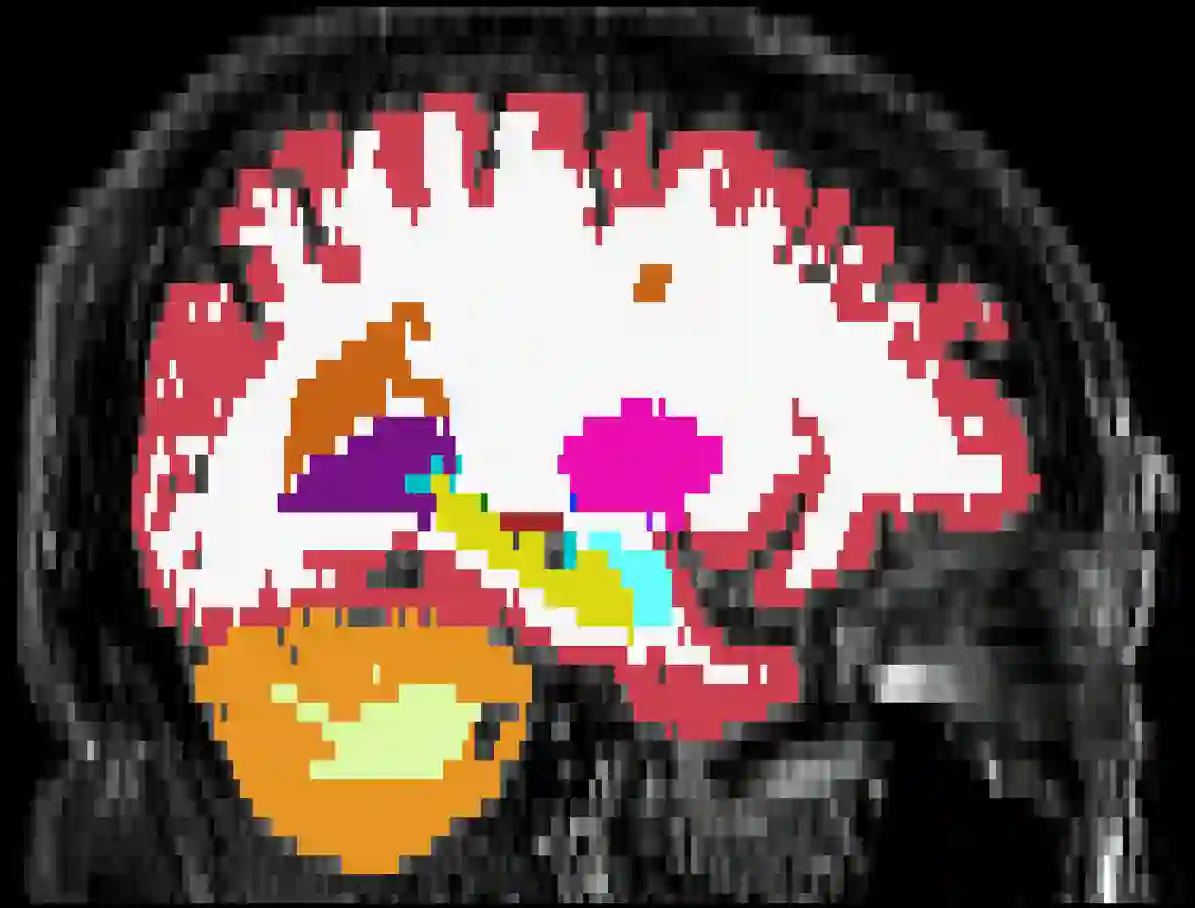

Brain atrophy and white matter hyperintensity (WMH) are critical neuroimaging features for ascertaining brain injury in cerebrovascular disease and multiple sclerosis. Automated segmentation and quantification is desirable but existing methods require high-resolution MRI with good signal-to-noise ratio (SNR). This precludes application to clinical and low-field portable MRI (pMRI) scans, thus hampering large-scale tracking of atrophy and WMH progression, especially in underserved areas where pMRI has huge potential. Here we present a method that segments white matter hyperintensity and 36 brain regions from scans of any resolution and contrast (including pMRI) without retraining. We show results on six public datasets and on a private dataset with paired high- and low-field scans (3T and 64mT), where we attain strong correlation between the WMH ($\rho$=.85) and hippocampal volumes (r=.89) estimated at both fields. Our method is publicly available as part of FreeSurfer, at: http://surfer.nmr.mgh.harvard.edu/fswiki/WMH-SynthSeg.